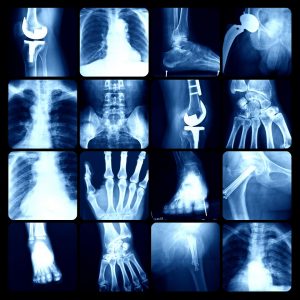

various different x-ray images from different body parts